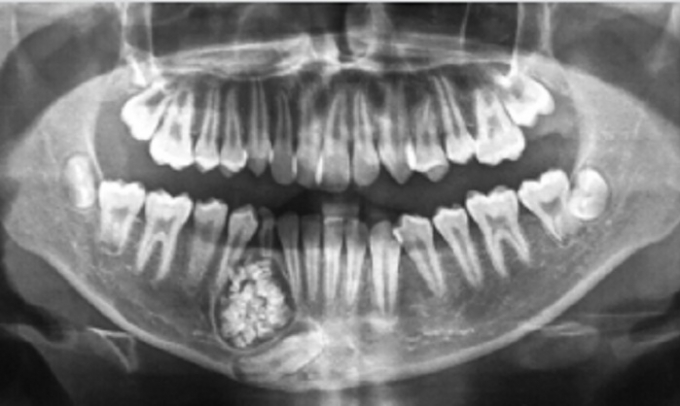

Khối u răng trong miệng cháu Kh. được phát hiện qua chụp X-quang.

Nguyên nhân do răng hàm dưới của cậu bé mọc lệch và chậm thay răng mới. Tuy nhiên, qua chụp X-quang, các bác sĩ phát hiện có một khối u răng ở xương hàm dưới. Sau khi hội chẩn qua hình ảnh, các bác sĩ của Bệnh viện Răng hàm mặt Trung ương TP.HCM đã ra Bệnh viện Đa khoa tỉnh Khánh Hòa thực hiện mổ cho bệnh nhi.

Sau một tiếng đồng hồ phẫu thuật, các bác sĩ đã lấy ra gần 100 chiếc răng nhỏ li ti có đầy đủ thân răng, tủy răng và chân răng từ khối u của bệnh nhân. Bác sĩ Tuấn cho biết, u răng hay còn gọi là ComplexOdontoma, là một trong những loại u lành tính và rất hiếm gặp ở nước ta. U thường diễn tiến âm thầm, ít gây ra triệu chứng nên khó phát hiện sớm.

U răng rất khó phát hiện, chỉ qua phim chụp Xquang mới có thể nhìn thấy. Chính vì thế, rất nhiều bệnh nhân điều trịsai cách, loại bỏ u không triệt để, nên bệnh tiến triển ngày một nặng, dẫn đến gãy xương hàm, đứt dây thần kinh.